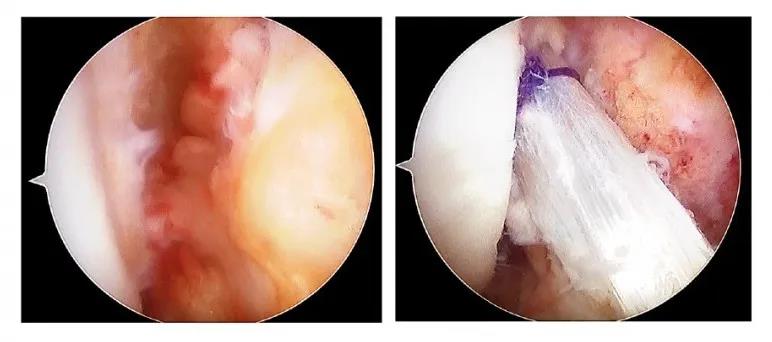

前十字韧带重建合并外侧肌腱固定特殊编织方法

因此,透过特别的韧带编织方法,可同时达到前十字韧带重建与外侧肌腱固定,提供充足的稳定度。适合术前有高度膝关节旋转不稳定、需要快速即停、转身动作的运动员,首次重建失败过后、与有严重前后关节不稳定的患者。

图左:前十字韧带断裂手术前

图右:前十字韧带重建合并外侧肌腱固定手术后